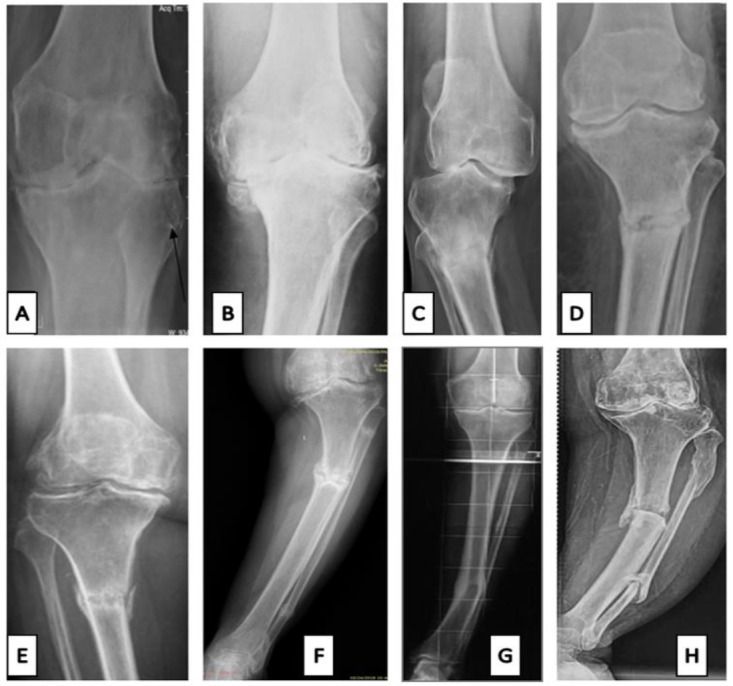

Objectives: Knee osteoarthritis (KO) is a leading contributor to disability years, with a prevalence ranging from 22% to 39%. Tibia stress fractures (TSFs) are well-described for end-stage arthritis patients undergoing TKA. Literature is ambiguous, with a wide range of management options. This study primarily aims to compare and determine the clinical, functional, and radiological outcomes of TSFs in end-stage KO treated with TKA by propensity score-based matching.

Methods: It is a retrospective, single-center, comparative study conducted at University Teaching Hospital. The institutional medical records (IMRs) database was inquired. The TSF group included all patients of end-stage KO who underwent primary TKA with TSFs, and the TKA group included matched patients without TSF. Cases were 3:1 (TKA: TSF) propensity score-matched (PSM). The primary outcome was a PSM comparison of patient-reported outcome measures (PROMs) and 1-year Postoperative Complications and Adverse Events (POCAE). PROMs included the knee society score (KSS), patient satisfaction (PS), and KSS functional activities (FA) score.

Conclusion: End-stage KO patients with coexisting TSFs who undergo primary TKA with stem/ plate fixation as per fracture location may expect favorable PROMs, POAECs, radiological outcomes, and rates of achieving the MCID at a minimum 2-year follow-up. Accurate management of such cases results in excellent outcomes and minimized revision rates. All patients achieved complete bone union. These results were comparable to the PSM control group.